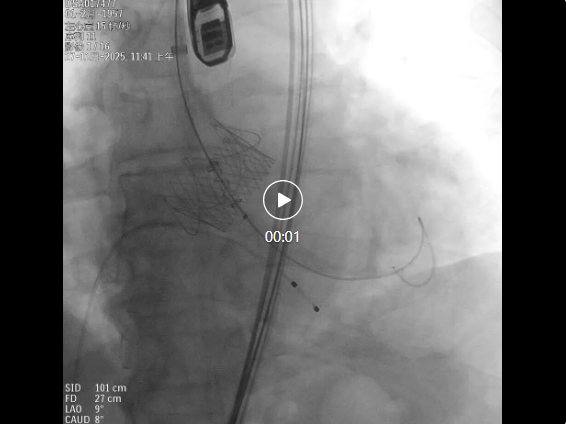

手术医生首先在汤爷爷右侧大腿根部进行穿刺,成功建立起一条细微的通道。随后,在血管造影的实时导航下,被压缩的人工瓣膜顺着导管,沿着血管的天然路径,精准抵达心脏的病变位置。

洪浪教授团队手术中

“瓣膜准备释放。” 洪浪院长沉稳的声音在手术室内响起。此刻,手术室内所有医护人员都屏息凝神,目光紧紧锁定在屏幕上。人工瓣膜如同花朵般缓缓展开,完美贴合在心脏瓣膜位置。紧接着,超声检查实时确认:反流消失,新瓣膜工作状态正常!

复查造影瓣膜固定,工作良好